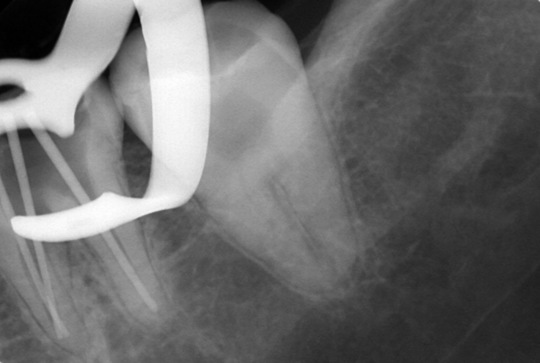

自費根管治療症例1 治療前

左上の奥歯の腫れと噛んだ時の痛みで来院。

根の先にうみが溜まっています

副鼻腔の骨の壁を突き破っています